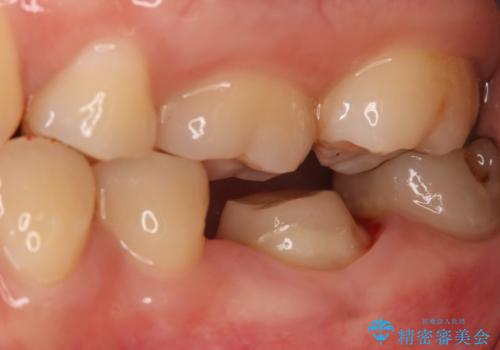

- 左下大臼歯の歯肉に腫れと痛みが繰り返し起こっているので治療を希望し来院された患者様です。

既に治療されている歯でしたが根尖部に病巣が確認出来たので、精密根管治療とクラウンの再治療が必要と判断されました。

精密根管治療を行なったことで病巣は消失し、腫れや痛みは再発することなく経過は良好です。

被せ物はフルジルコニアクラウンを選択されました。